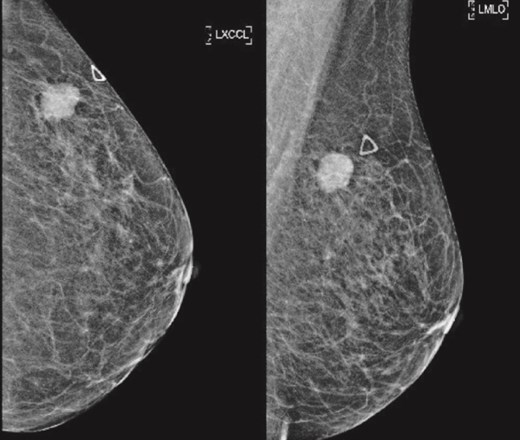

Patient C, aged 70, had no significant past medical history and initially presented to Otolaryngology with right-sided cervical lymphadenopathy. Excision biopsy confirmed a diagnosis of diffuse large B cell lymphoma (DLBCL). She then reported a 3-month history of a left breast lump. Clinical examination and imaging revealed a 20 mm lesion associated with ipsilateral axillary lymphadenopathy (Figs 7 and 8). Triple assessment confirmed triple negative invasive ductal carcinoma in the breast, whilst there were follicular cells in the nodes (Fig. 9). She underwent systemic chemotherapy for stage III diffuse large B-cell lymphoma using Rituximab, cyclophosphamide, doxorubicin, vincristine, and prednisolone (R-CHOP) protocol followed by weekly Paclitaxel for the concurrent breast cancer. She achieved clinical remission for lymphoma. Subsequently she underwent breast conserving surgery with sentinel node biopsy, and adjuvant chest radiotherapy.

(Left) Mammography cranial-caudal view of left breast; (Right) Mammography mediolateral oblique view of the left breast: Left upper outer breast spiculated mass with minimal architectural distortion.